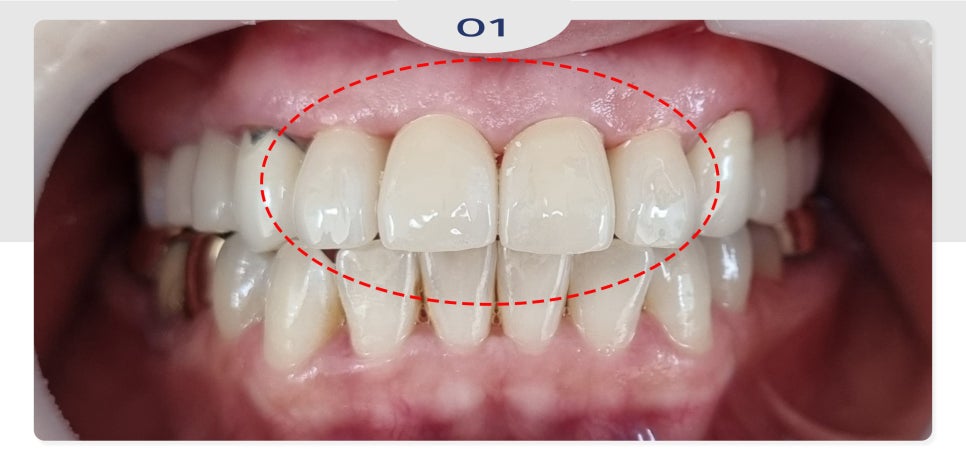

24.11.22

이후 조금 더 심미적인 목적으로

4개의 앞니를 지르코니아 크라운

보철로 완료하였습니다.

기존의 오른쪽 송곳니 PFM 보철도

파절로 보이긴 하였으나

환자분의 사정으로 인해

추후 진행 예정이십니다!

환자분께는 원하는 모양과 색상으로

보철이 완성되어 매우 만족해하셨으며

빨리 송곳니도 하고 싶으시다고

말씀해 주셨습니다.